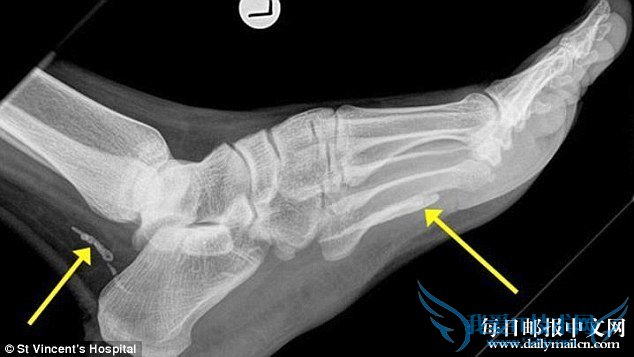

男子脚部和脚踝处蜷缩着两截几厘米的几内亚龙线虫尸体

这位38岁的男子四年前移民至澳大利亚的墨尔本居住,大约在1年前男子的脚部就开始肿胀、疼痛。入院治疗后,医生乔纳森说:“X光显示该男子脚部和脚踝处蜷缩着两截几厘米的几内亚龙线虫尸体。而几内亚龙线虫一般可以长到一米左右,可能是因为虫子在男子体内早已死亡,虫体在体内开始退化。”两截虫体已被取出,男子的脚已无大碍。